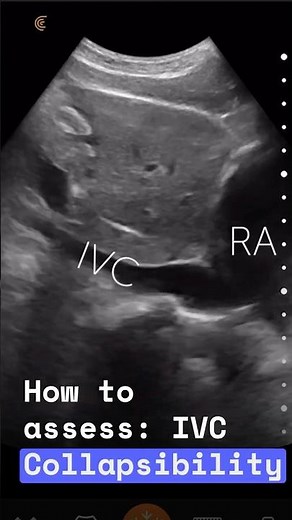

IVC Collapsibility Index 的热门建议 |

- IVC

Distensibility Index - IVC

USG Collapsibility - IVC